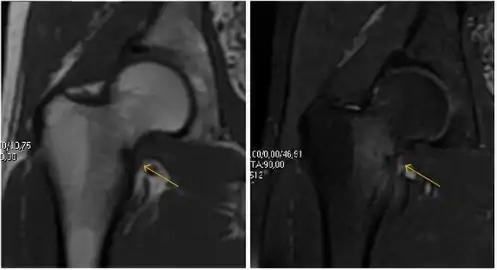

Most of the angles and measurements described in the plain radiograph section can be accurately reproduced on MRI. In addition, the superiority of MRI resolution with intra-articular contrast allows detection of labral and chondral abnormalities that may influence the choice of medical, percutaneous, or surgical management (Figure 9).[1]

Figure 9:

MR arthrography has proven superior in accuracy when compared to native MR imaging. It is considered the best technique to assess the labrum. Knowledge of the normal variable morphology of the labrum helps to differentiate tears from normal variants. A triangular shape is most commonly seen in 66% of asymptomatic volunteers, but round, flattened, and absent labra can also be found in asymptomatic populations. MR arthrography has demonstrated sensitivity over 90% and specificity close to 100% in detecting labral tears. Loose bodies are demonstrated as filling defects surrounded by the hyperintense gadolinium.[1]

MR arthrography can also demonstrate ligamentum teres rupture or capsular laxity, which are debated causes of microinstability of the hip. Elongation of the capsule or injury to the iliofemoral ligament or labrum may be secondary to microtrauma in athletes. MR can demonstrate abnormalities in these cases, such as increased joint volume or a ligamentum teres tear (Figure 9).[1]